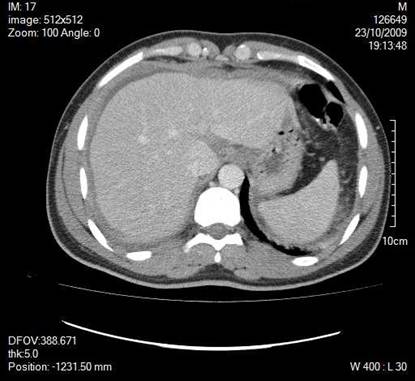

A 30-year old man presented with symptoms and signs of acute appendicitis. Abdominal imaging via ultrasound and computed tomography detected a mass in the right iliac fossa. Exploratory laparotomy revealed an appendiceal mass and gelatinous peritoneal fluid, while histopathology confirmed the diagnosis of pseudomyxoma peritonei arising from a mucocele of the appendix and attributed to an appendiceal cystadenocarcinoma. The clinical and imaging findings of this rare case are herein presented.